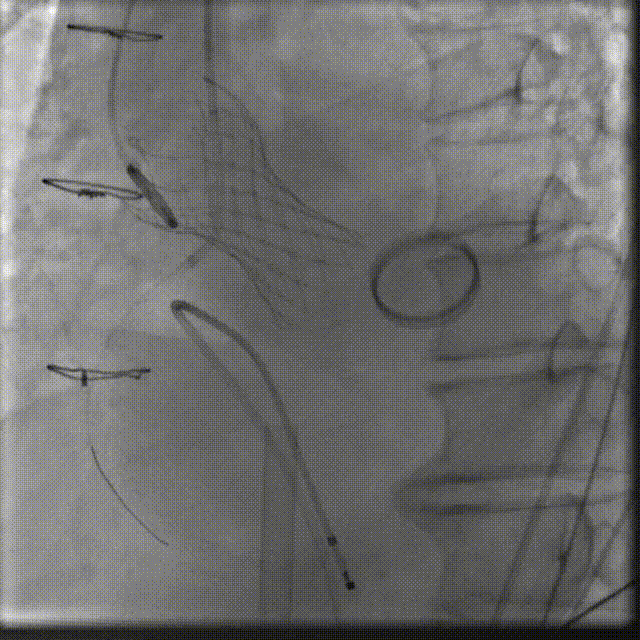

初冬的塞上大地,贺兰山脉覆着薄霜,黄河之水仍漾着温润波光,苍茫辽阔的西北风光里,藏着独有的坚韧与温情。这片孕育了西夏文化、承载着丝路底蕴的热土,自古便有着守望相助的人文情怀,而守护生命安康,更是这里医者们从未动摇的使命。在这片土地的医疗高地宁夏医科大学总医院,由刘旭东教授、李晓东教授、张玉京教授组成的心脏瓣膜专家团队,近日以一场高难度的创新手术,为心血管疾病患者点亮了新生希望 —— 成功完成全球首款预装干瓣 ProStyle A® 的全国首批临床植入。 此次手术的患者病情特殊,不仅主动脉瓣中度狭窄合并中 - 重度关闭不全、瓣叶增厚,还曾接受二尖瓣位机械瓣植入术,瓣膜锚定难度极大。团队历经多轮严谨评估,最终敲定采用 ProStyle A® 介入治疗方案,凭借精湛医术与周密预案精准完成瓣膜释放。这场手术的成功,标志着医院在结构性心脏病介入治疗领域迈入全生命周期管理新阶段,也成为国产创新器械与临床智慧深度融合的重要里程碑。 刘旭东教授 宁夏医科大学总医院 传统戊二醛保存的瓣膜,长期使用中易因组织钙化、柔韧性下降导致功能衰减。但 ProStyle A® 的优势在于两点:一是金仕生物的专利抗钙化技术,通过纳米级工艺去除组织内细胞碎片与磷脂,同时封闭游离醛基 —— 这相当于从源头阻断了引发瓣膜钙化的‘关键诱因’;二是干式存储技术,最大程度保留了心包组织原有的亲水亲油平衡,让瓣叶始终维持天然的曲柔性,确保长期开合功能稳定。对像此次手术这样的心功能受损患者来说,这种‘抗钙化 + 保柔韧’的双重设计,意味着瓣膜能更长时间地维持正常功能,减少二次干预的风险,真正实现‘一次植入,长期获益’,这正是全生命周期管理理念在器械选择上的核心体现。” 患者病史 主诉:反复胸闷气短2月余 术前超声提示:二尖搬位机械置换术后,功能未见明显异常,瓣周返流(轻-中度) 主动脉瓣狭窄(中度)并关闭不全(中-重度)VP:3.3mm/s,PG:45mmHg 三尖瓣返流(轻度) 左房显著增大左室明显增大主肺动脉增宽 左室收缩功能明显减低 术前CT 三叶瓣,瓣叶增厚轻度钙化,主动脉根部直径27.8mm,LVOT直径34.7mm。 双侧冠脉开口高度尚可,左右冠切线角度测量右冠瓣叶长于冠脉开口上缘到根部距离,瓦氏窦偏大。 左室腔扩大,EF较低,有一定循环崩溃风险,主动脉瓣环水平夹角52.7度,非横位心患者,主动脉弓宽度、角度可;二尖瓣机械瓣(横列式)置换术后AV-MV夹角130度,距离主动脉瓣虚拟瓣环6.67mm。 外周走行尚可,全主动脉基本无钙化,右股低分叉,血管内径可,血管内壁存在纤维增厚。右侧为主入路能够支持20F大鞘通过。 手术策略 右侧股动脉为主入路,预装ProStyle A® AV32主动脉瓣膜,使用20F大鞘,不预扩,建议最终理想释放位置0-瓣下2mm。 手术过程 在右股动脉穿刺建立通路后,将右冠送入冠脉保护,后顺利送入大鞘,经食道超声及血管造影确认路径稳定,将ProStyle A® AV32号瓣膜精准释放于目标位置(瓣下2mm),超声显示无瓣周漏,平均跨瓣压差4mmHg,心功能明显改善,患者生命体征平稳。 右冠保护 同时主动脉根部造影 定位 缓慢释放瓣膜 最终造影,位置形态良好,冠脉充盈良好 术后超声:显示瓣膜呈现较好的圆形,最大流速133cm/s,平均跨瓣压差显著降低至4mmHg,瓣周无反流。 ProStyle A®预装干瓣——助力临床最优化解决方案: 平衡径向支撑力:ProStyle A®瓣架网孔比例按照病例解剖结构的特殊设计,使瓣膜在狭窄最重的地方良好的撑开, 同时避免对瓣环及周边组织的过度压迫,有效降低传导阻滞风险。 精准释放:底部桶状设计更易迅速锚定,协同释放张力小,助力最终精准释放; 80%可回收设计:对于复杂解剖结构的患者,提供更充分的调整窗口,显著提升释放安全性与精准度并且80%可回收设计在释放过程中给予术者充分的容错空间。 预装干瓣 便捷顺安:金仕生物专利抗钙化技术运用纳米技术去除组织内的细胞碎片和磷脂,封闭游离醛基,从根本上阻断了瓣膜钙化的多项因素,显著提升了瓣膜的耐久性;同时,相比较传统戊二醛保存方式,干式存储最大限度的保留心包的亲水亲油平衡,还原组织天然曲柔性,进一步保障了瓣叶开合,保证长期耐久性。 专家简介 刘旭东 宁夏医科大学总医院(点击查看专家详细简历) 李晓东 宁夏医科大学总医院(点击查看专家详细简历) 张玉京 宁夏医科大学总医院(点击查看专家详细简历) · END ·